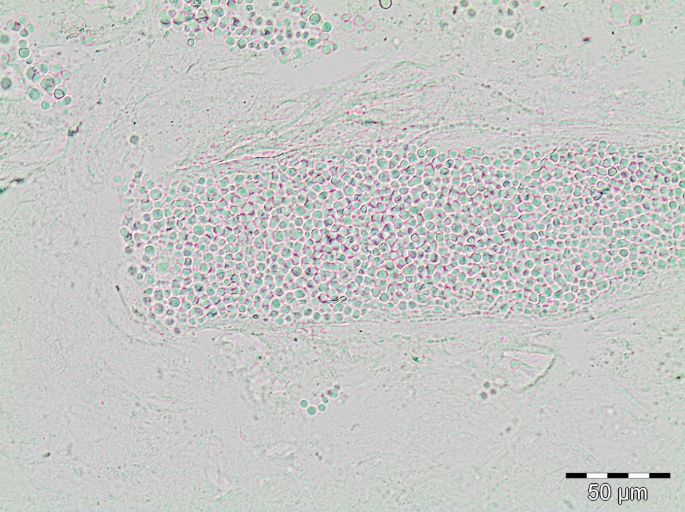

Infectie treedt op na adhesie van de sporen aan niet-levende cellen (keratinocyten) van de bovenste huidlaag (stratum corneum). De sporen ontkiemen, waarna adhesie, vermenigvuldiging en invasie van de schimmel plaatsvindt. Een predisponerende factor hierbij is een toegenomen vochtigheidsgraad van de huid. Vanuit de plaats van infectie groeien hyfen, schimmeldraden, het stratum corneum in. Van daaruit worden de haarzakjes aangetast en windt de schimmel zich, afhankelijk van de schimmelsoort, om de haarschacht heen of wordt opgenomen in de nieuw gevormde haren. Tinea capitis wordt geclassificeerd op basis van de plaats waar de sporen zich ten opzichte van de haar bevinden. De sporen kunnen zich bevinden op de haar: ectothrix, of binnen in de haar: endothrix. Bij ectothrix tinea capitis (onder andere M. canis) bevinden zich de sporen in het haarzakje en aan de buitenkant van de haar. Dit leidt na enkele weken tot destructie van het haarzakje en dus tot alopecia. De haren worden broos en breken af. Bij endothrix tinea capitis (onder andere T. tonsurans en T. violaceum) bevinden de arthroconidia (sporen) zich in de haarschacht. Destructie van het haarzakje treedt hierbij niet op. Ectothrix en endothrix hebben niet alleen betrekking op de vorming van sporen maar ook op de groei van de schimmel zelf, bij endothrix groeien ook de hyfen in de haar en vormen daar arthroconidia.